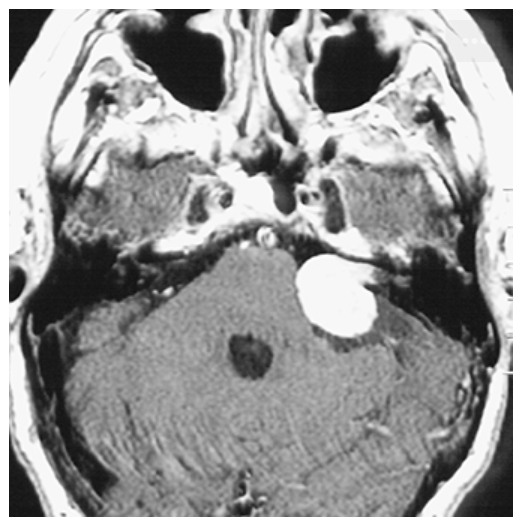

Acoustic Neuroma. Postcontrast T1-weighted axial image demonstrating an intense contrast enhancing extraaxial mass at the left cerebellopontine angle close to the left internal auditory canal (IAC) consistent with an acoustic neuroma.